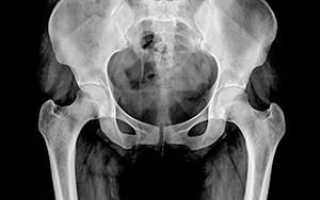

Рентген — один из самых доступных и информативных методов лучевой диагностики болезней тазобедренных суставов (ТБС). На снимках хорошо визуализируются вывихи и переломы, видны аномалии в строении костной ткани. Наряду с клиническим обследованием, рентгенография является основой для постановки диагноза и выбора тактики лечения при заболеваниях ТБС.

Базовой считается обзорная рентгенограмма тазовой области в прямой проекции. Понятием «проекция» обозначают ход центрального рентгеновского луча, выходящего из вакуумной трубки, в теле пациента. Помимо обзорного снимка, дополнительно выполняют рентген в боковой или косой проекции.

В положении больного на спине исследуются тазобедренные суставы по отдельности и область всего таза. Пучок рентгеновских лучей фокусируется перпендикулярно плоскости тела (отвесно) — в прямой проекции (еще ее называют «переднезадней»).

При осмотре таза обе ноги вытянуты, стопы ротированы внутрь на 15°, большие пальцы соприкасаются. Центральный луч направляется на лонное сочленение.

При подозрении на перелом шейки бедра стопы не ротируются. В результате получают снимок обеих половин таза, на котором просматриваются границы ветлужной впадины, ветви лобковых и седалищных костей, межпозвонковые отверстия крестца и область соединения ноги с тазом.

После завершения съемки врач-рентгенолог проводит их расшифровку. Оцениваются все элементы сустава, величина суставной щели; фиксируются отклонения от нормы взаимоотношения костей, образующих ТБС.

В норме головка бедренной кости округлая. Ямка головки видна в виде углубления у медиальной поверхности бедренной кости. Большой вертел находится на линии между верхней передней подвздошной костью и седалищным бугром. На рентгене контуры суставной щели четко очерчены.